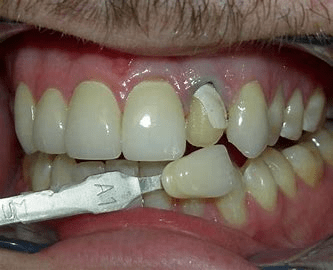

Broken Veneers, Crowns, or Teeth

If a dentist only covers these issues with veneers without fixing the root cause, of why these teeth are breaking in the first place, these problems will persist. This quick fix can lead to veneers coming off or breaking again. Natural teeth may wear down faster due to the softer enamel compared to porcelain. Covering the problem doesn’t solve it for long; it merely hides the issue until it resurfaces elsewhere. Dr. Babcock, and Dr. Lilit will identify and treat the root cause of underlying problems.